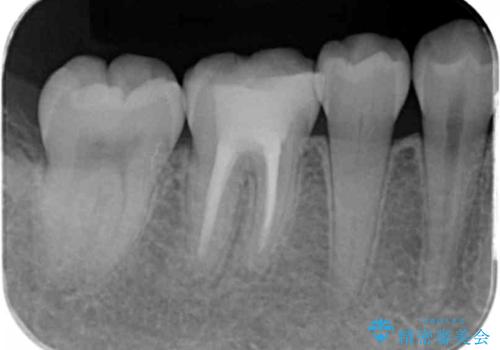

- 樹脂をやり替えたいとのことで来院されました。

特に大きな虫歯もありませんでしたが、残った歯が薄かったためクラウンでの修復処置を行いました。

インレーにすると残った歯が薄くなってしまう場合は術後の破折リスクが高いためクラウンで修復することがあります。